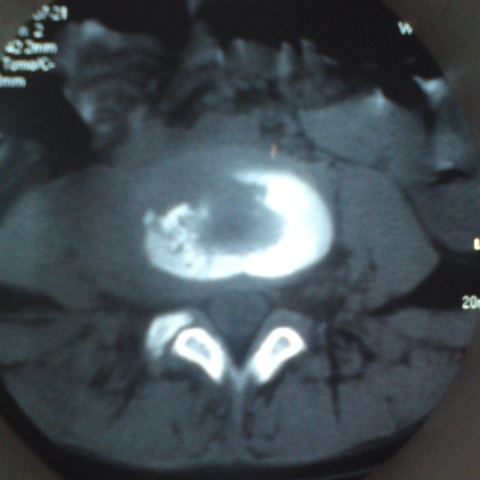

标题: CT27836:女 ,13岁,腰痛数月,加重一月,检查下腰部明显压 [打印本页]

标题: CT27836:女 ,13岁,腰痛数月,加重一月,检查下腰部明显压

考虑腰4椎体结核伴右侧椎旁及椎管右侧硬脊膜外脓肿形成。

建议椎体扫描连续层面观察或mri看看,是脓肿还是软组织肿块,tb脓肿很少到后方来的,肺部有无tb灶。

考虑腰椎结核伴右侧椎旁及椎管右侧硬脊膜外寒性脓肿形成;建议必要时行mri检查。